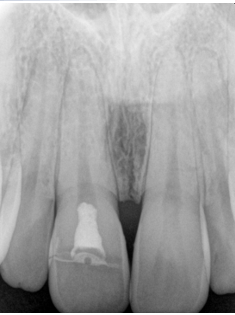

A 22-year-old patient presented to a prosthodontic practice with an complicated fracture of a maxillary central incisor (Fig. 1). The patient was transported to the dental clinic after experiencing trauma to the maxillary anterior teeth during physical fitness training. #8 displayed a mid-crown complete horizontal fracture, the pulpal tissue was exposed, no mobility, and the patient reported a moderate amount of sharp constant pain (Fig. 2). A pulpal and periapical diagnosis of symptomatic irreversible pulpitis and normal apical tissue was made. No other injuries were noted to adjacent teeth or intraoral and extraoral tissue. The fractured segment was brought with the patient and after cleaning with sterile saline it could be easily aligned back on the tooth and the margins displayed a clean fracture (Figs. 3 and 4). The patient was esthetically demanding and required a quick and long-term solution to return back to training as he was a student at Fort Eisenhower. The patient was scheduled for an overseas mission shortly after his school ended.

Figure 2: Close up of fractured maxillary central incisor.